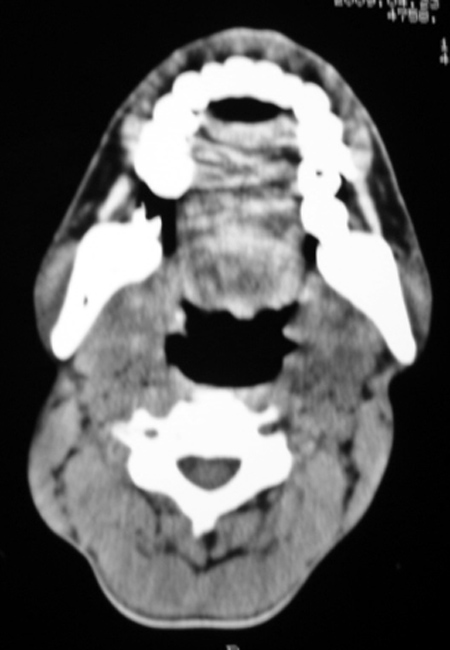

以下是引用syfszcw在2009-4-23 13:21:00的发言:[br]双侧上颌窦 筛窦慢性炎症,鼻息肉 会厌ca[br][br][本贴已被 syfszcw 于 2009-4-23 13:36:46 修改过]

以下是引用随光逐影在2009-4-23 19:35:00的发言:[br]1)鼻咽、口咽、左侧鼻腔及右侧鼻后孔处新生物,考虑息肉可能性大。2)双侧上颌窦及双侧筛窦炎症,不排除双侧上颌窦内息肉可能。